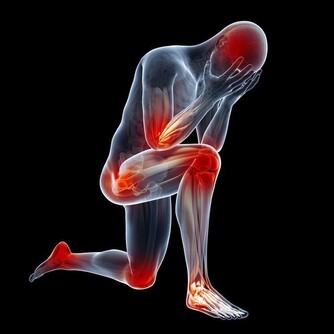

皮膚瘙癢,為什麼會越抓越癢?

撓抓皮膚,使得嬌嫩的皮膚表層被剝落脫掉,真皮層裸露,被細菌和真菌感染,產生炎症反應,因此越抓越癢。又因太用力,皮膚被抓破了真皮層,導致感覺又痛又癢,但是覺得還不解癢。如此抓幾次之後,更是引起表皮剝脫,進一步加重皮膚乾燥的問題,瘙癢感繼續加重,甚至嚴重到身體有點熱度時,身體就開始發癢。

身上癢癢癢,能不能撓?

皮膚瘙癢,人們出於本能會去撓,甚至使用各種工具,但這種做法往往會讓情況變得更糟。

過度搔抓會破壞皮膚的完整性,從而使瘙癢的情況加重,導致“越撓越癢,越癢越撓”的惡性循環,甚至引起繼發性的皮損和感染: